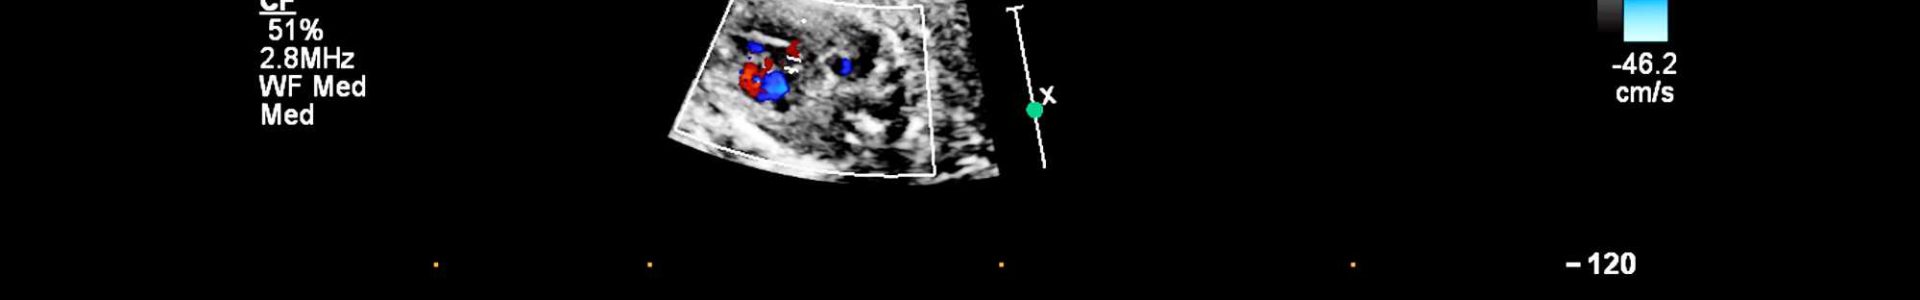

- Fluxos sanguíneos: Análise das direções e velocidades do sangue dentro do coração, verificando se está circulando adequadamente.